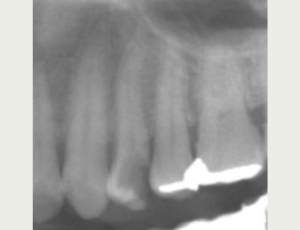

CASE 4

BEFORE

AFTER

基本情報

| 年齢・ 性別 |

30代・男性 |

|---|---|

| 主訴 | 歯が痛い・左下6 |

| 治療 内容 |

左下6・根管治療 (根管が曲がっている為細く曲がった歯の神経の治療に対応できる弾力が高く柔軟性 のあるニッケルチタンファイルを使用。 またラバーダムを用い防湿を行いながら治療 を進めました) |

| 治療 期間 |

2回 |

| 治療費 | 保険診療 約3,000円 |

| リスク・ 副作用 |

神経を取ってもすぐに痛みが引かない可能性があります。 神経の治療の刺激により、数日痛み・腫れがでる可能性があります。 細く繊細な器具を使用するため、器具が破折する可能性があります。 複雑な神経の治療では、大学病院もしくは専門医による治療が必要となることがあります。 または抜歯になることもあります。 |